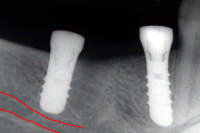

- Auf den Röntgenbildern von Abb. 3 und 4 sieht man den Verlauf eines sensiblen Nerves im Unterkiefer-Knochen (rot hervorgehoben). Dieser Nerv versorgt unter anderem die Unterkiefer-Lippe sensibel und darf bei der Implantation nie verletzt werden. Um dieses Ziel zu erreichen, wird vor jeder Implantation im Unterkiefer-Seitenzahngebiet ein Röntgenbild mit einer Metallkugel von 5 mm Durchmesser gemacht, um die Höhe des Knochens bis zu diesem Nerv in etwa zu berechnen (Abb 3).

In diesem Fall wurde der bis auf den Knochen abgefaulte eigene Zahn rechts der im Röntgenbild weissen Metallkugel gezogen (Abb. 3). Die absolute, genaue Berechnung der Höhe des Knochens bis zu diesem Nerv erfolgt während der Operation mit sogenannten Tiefenmesslehren (Abb. 4). Damit ist es mir möglich, das längenmässig richtige Implantat optimal in den Knochen und ohne Risiko einer Verletzung für den Nerv zu setzen (Abb. 5).